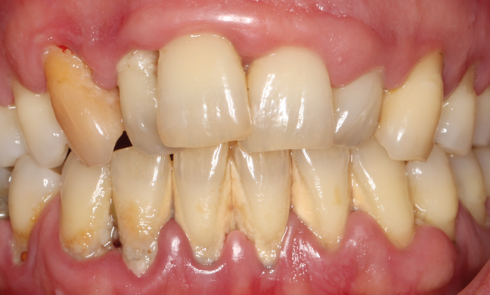

Article réservé à nos abonnés Nouvelle classification… et parodontite – stade III grade B #8

Qu’est-ce qu’une parodontite stade III grade A selon la classification de Chicago 2017 ? Il s’agit d’une parodontite sévère à...